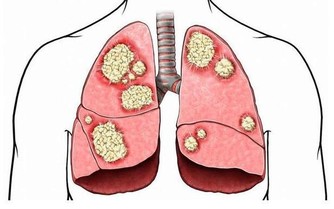

5、預防癌症

現在很多人都是很喜歡吃雞蛋的,在很多菜餚中,也都有著雞蛋的身影,雞蛋中含有的維生素B2對人體是很不錯的,有助於氧化致癌物質,而經常吃韭菜煎蛋的話,也有一定預防癌症的作用了。